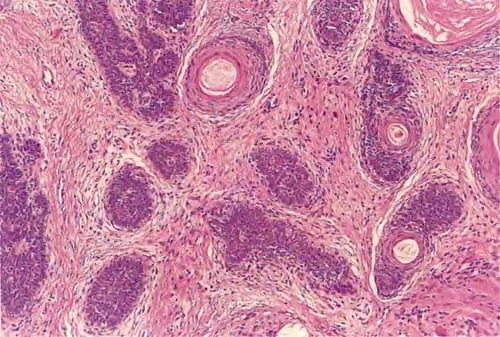

Read MoreTrichoepithelioma =ورم ظهاري شعري Trichoepithelioma Trichoepithelioma occurs either in multiple lesions or as a solitary lesion. The name trichoepithelioma is preferable to other designations, such as epithelioma adenoides cysticum and multiple benign cystic epithelioma, because it is more indicative that the differentiation of this tumor is toward hair structures. Multiple trichoepitheliomas are transmitted as an autosomal dominant trait (53). In most […]